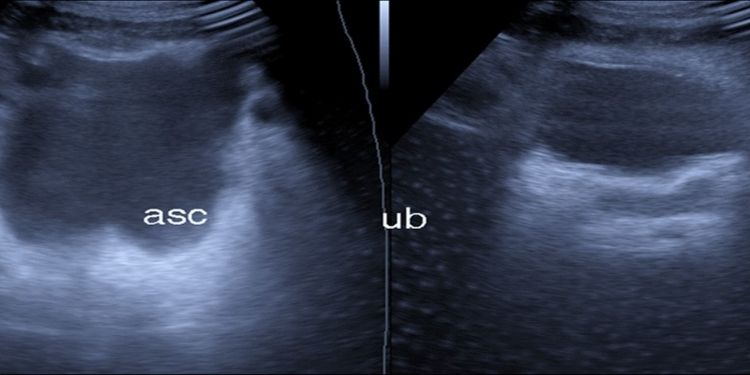

University of Obafemi University, Department of Oral and Maxillofacial Surgery and Oral Pathology, Ile-Ife.